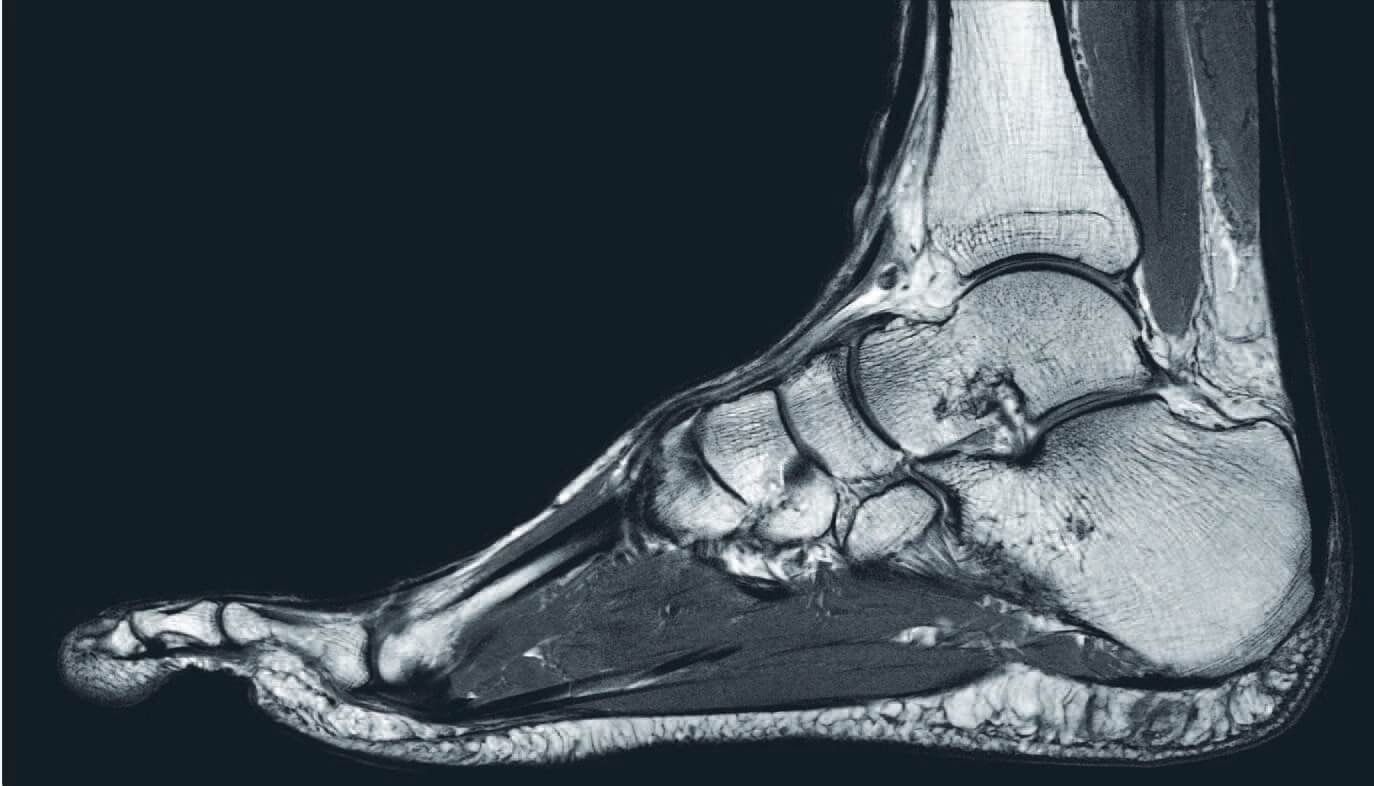

Orthopedic